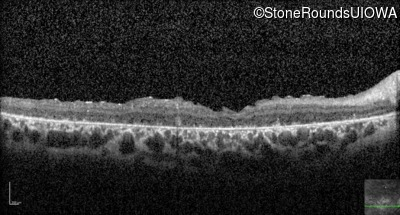

Optical Coherence Tomography - Right - Count Fingers 3'

Exemplar / OCT Stack